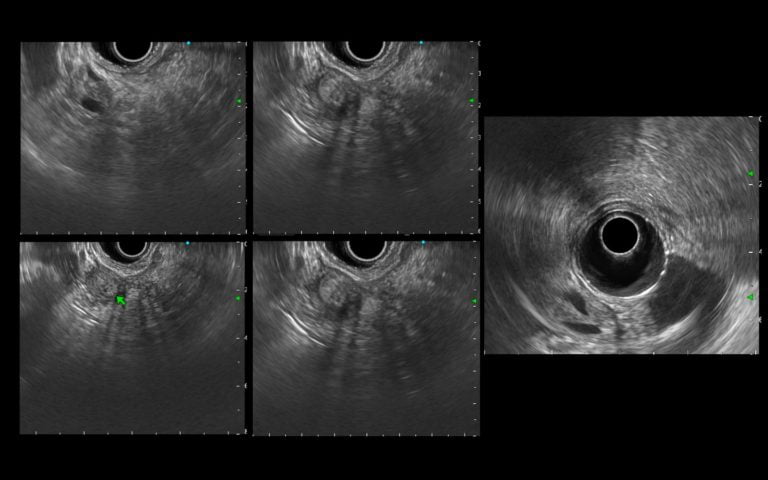

An endoscopic ultrasonography (EUS) was performed and identified a hyperechoic thickening of the ampulla, with clearly defined regular borders, without intraductal infiltration, biliary or pancreatic duct dilation (Fig. 1).

Figure 1. EUS (transduodenal view): A heterogeneous hyperechoic thickening of the ampulla, with a clearly defined regular border, without intraductal infiltration, biliary or pancreatic duct dilation.